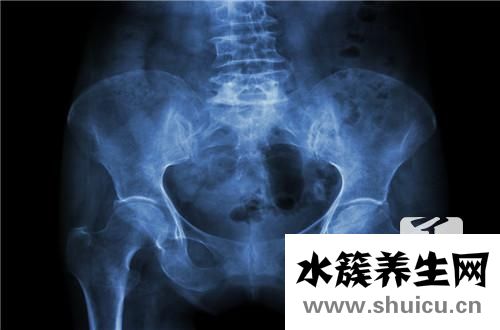

為了評估盆腔腫塊是好還是惡性,可以根據常規血液檢查中的白細胞計數來判斷。 任何患有骨盆腫塊的人都應該去正規醫院進行詳細檢查。 由于該疾病具有許多可變性,因此如果不進行詳細檢查,則人眼無法分辨出該疾病的某些特征。

盆腔包塊的血常規化驗可查驗白細胞計數,10x109/L,以單核細胞上升主導。

盆腔包塊的全身及婦科體檢因為變病水平與范疇的不一樣而有很大差別,較多病人因不孕癥行診斷性刮宮才發覺身患子宮壁結核病,而無顯著臨床癥狀和別的主動病癥。較比較嚴重病人若有腹膜后結核病,查驗時腹部有柔韌性感或肝腹水征,產生包裹性積液時,可碰觸囊性硬塊,界限不清,不活動,表層因為有腸道黏連,叩診空響。孑宮一般生長發育較弱,通常因周邊有黏連使活動受到限制。若附件累及,在孑宮兩邊可碰觸大小不一及樣子不規律的硬塊,質硬、表層高低不平、呈包塊或乳頭狀凸起,或可碰觸增厚包塊。